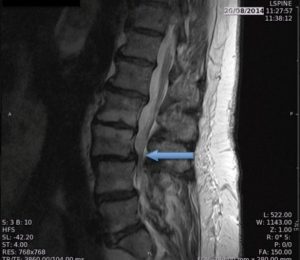

Obstrução severa nos nervos intra-espinhais produzidos por depósitos de gordura no canal (em cinza na ressonância magnética)